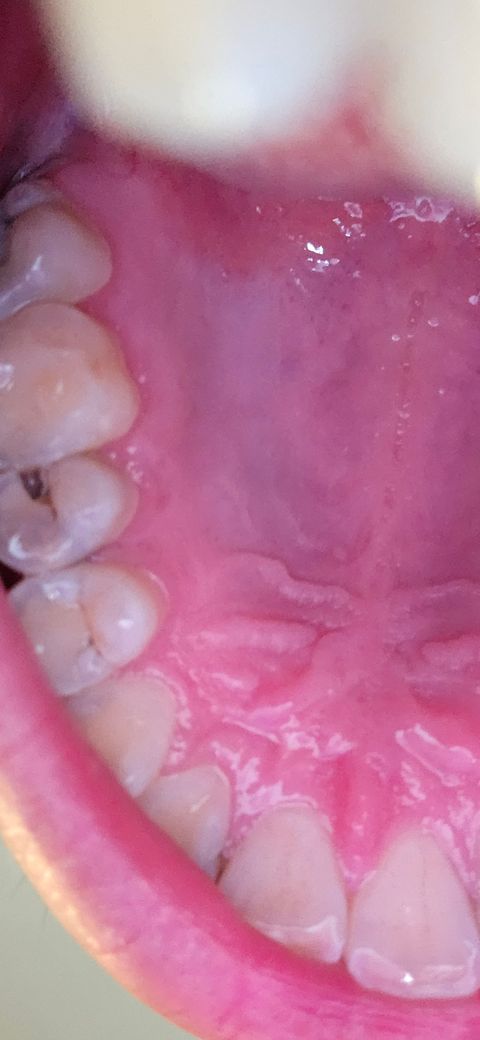

어금니에 구멍이 났어요 치료를 늦출수있을까요

이번에 치아가 아파서 확인하니 어금니에 구멍이 있더라거요 ㅠㅠ 제가 2달뒤에 1년동안 준비한 전문직 시험이 있어서 지금 치료를 받을지 고민 되는데 월요일이라도 바로 갈까요 ㅠㅠ 질문드립니다

• 1번 째 사진

치아 안쪽으로 충치가 많이 진행된 것으로 보입니다. 아마도 신경 가까이 까지 충치가 진행되어 신경치료 까지 생각해야 합니다. 지금 당장 통증이 없다면 2달 동안 기다려 보는 것도 생각해 볼 수도 있지만 가능한 빨리 치료하는 것이 좋습니다.

사진으로 보이는 충치는 인접면에 깊게 생긴것으로 보입니다

인접면 충치는 시간이 지나면서 크게 진행되기 때문에 빠르게 치료해 주는 것이 좋습니다

충치의 범위가 커 신경까지 감염이 확산 된 경우 큰 통증과 함께 치료에 시간이 많이 듦으로

발견 즉시 치과 내원하여 검사 후 치료 받아주는 것이 좋습니다

지금도 충치가 많이 진행된거 같습니다. 신경치료까지 해야될 가능성이 높으니 빨리 치과에 가셔서 치료를 받으시는게 좋습니다.

두달동안 방치하기에는 크기나 위치가 좋지않습니다.

치과를 빨리 가서 치료를 하시는게 좋겠습니다